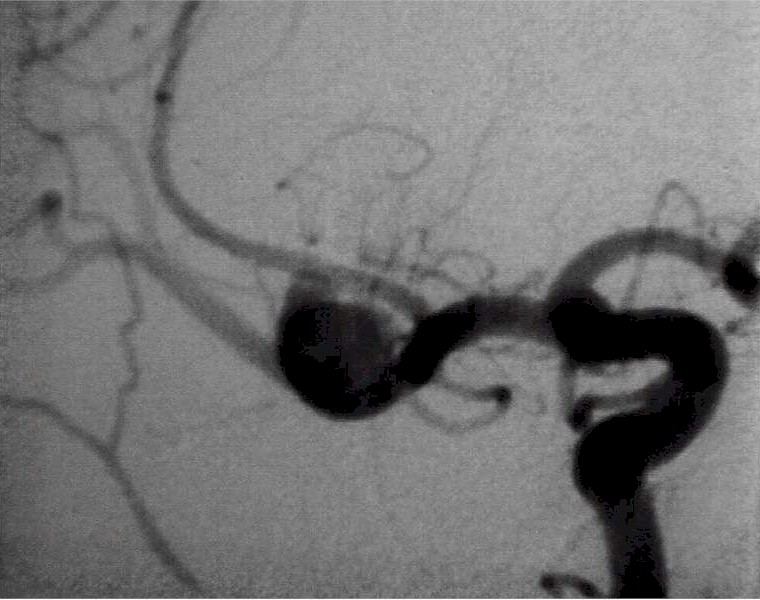

|

Duplice aneurisma: da un

lato esclusione con clip (freccia gialla), dall'altra con spirali. |